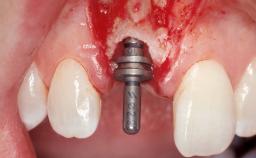

Immediate Flapless Placement of an Implant in a Maxillary Right Lateral Incisor Site

This 43-year-old male patient, a non-smoker, came to our practice because of a fracture of tooth 12 caused by a bicycle accident. Due to the combined para- and infrabony crown and root fracture, tooth extraction, and subsequent implant placement were suggested to the patient as the therapy of choice. The patient had high esthetic expectations with regard to the treatment outcome and asked for an immediate fixed provisional restoration. His individual esthetic risk profile summed up to a medium esthetic risk.

Placement Protocol Immediate implant placement

Tooth Site Maxillary incisor or canine

Socket Morphology Single-root socket

Socket Integrity Sufficient, with intact bone walls